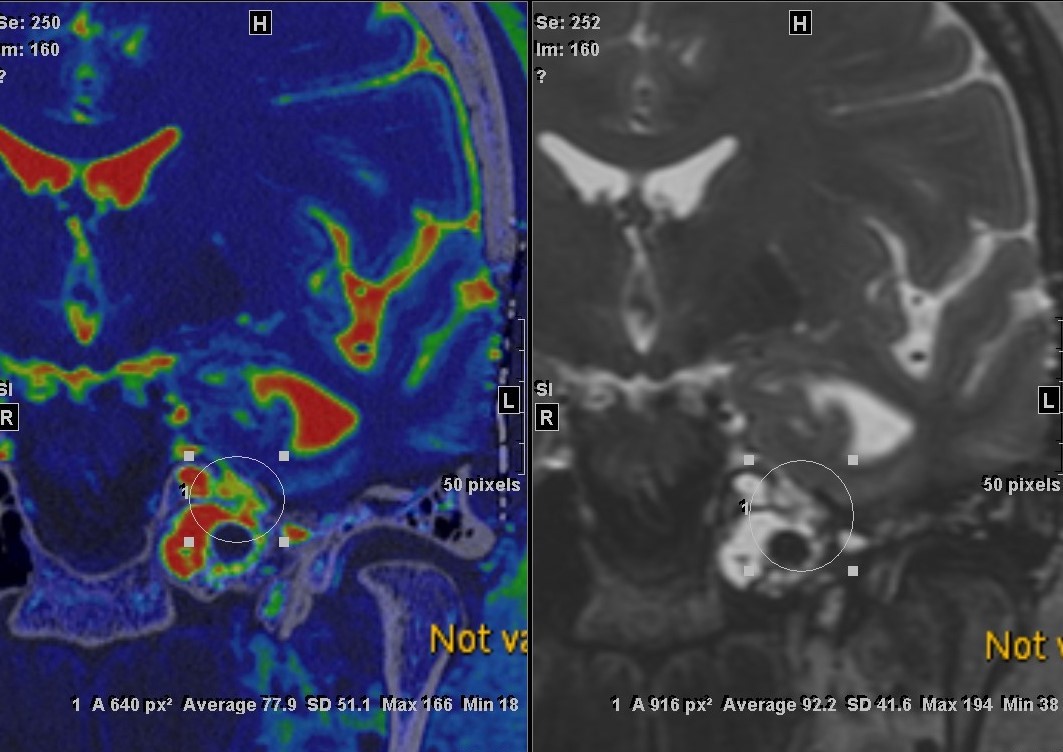

After 3 months, she complained of intermittent clear drainage from the tube. A fluid sample was positive for beta-2-transferrin. CT-MRI fusion imaging revealed a fluid tract medial to the original repair, at the petrous apex at Meckel’s cave (Fig. 4). A ventriculoperitoneal shunt was performed and the leak resolved.

Figure 4

This case illustrates that certain cases of CSF otorrhea can become chronic if they are not diagnosed. A transcranial approach is necessary if the site of leakage cannot be accessed through the mastoid. Increased intracranial pressure may be a cause of failure of direct repain, and may require the placement of a ventriiculoperitoneal shunt.